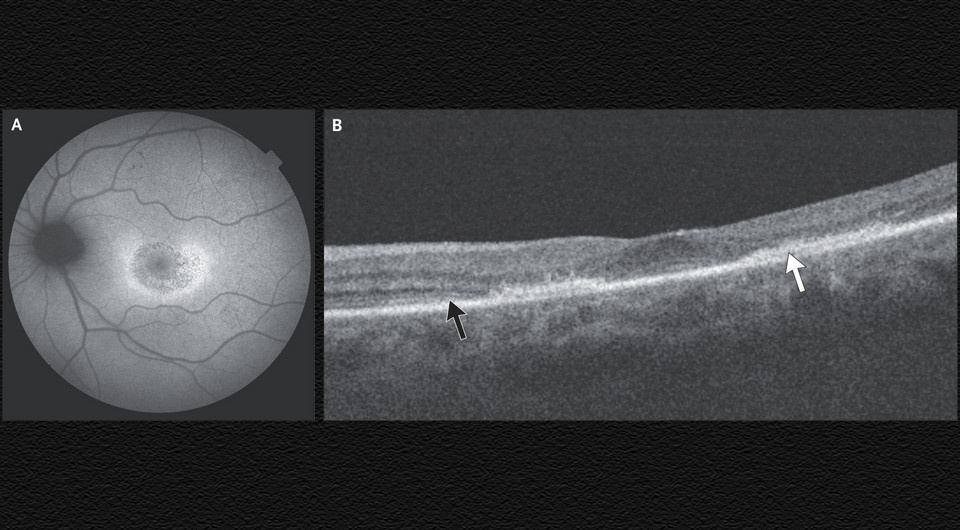

Aaron Donnelly, Noel Horgan / NEJM, 2025

К врачам Аарону Доннелли (Aaron Donnelly) и Ноэлу Хоргану (Noel Horgan) в Университетскую больницу Сент-Винсент для планового офтальмологического обследования поступила 71-летняя женщина с системной красной волчанкой. В течение последних 15 лет она принимала 200 миллиграмм (3,3 миллиграмма на килограмм массы тела) гидроксихлорохина в день в качестве базовой терапии. Изменений зрения женщина не отмечала, при осмотре острота зрения была нормальной.

При офтальмоскопии визуализировалась гипопигментация желтого пятна обоих глаз по типу «бычьего глаза». Аутофлуоресценция глазного дня определила повышенное накопление липофусцина («пигмента старения», который откладывается в неделящихся клетках) в парафовеолярных областях пигментного эпителия сетчатки обоих глаз. При оптической когерентной томографии наблюдалось утончение наружных слоев сетчатки с миграцией в них пигментного эпителия.

По данным обследования женщине поставили диагноз токсического поражения сетчатки обоих глаз гидроксихлорохином — дозозависимой пигментной ретинопатии. Ежегодный скрининг на подобные состояния показан всем пациентам, принимающим гидроксихлорохин в дозе более пяти миллиграмм на килограмм массы тела или в любой дозе дольше пяти лет. При своевременном выявлении, как в этом случае, прогноз обычно благоприятный. Терапию гидроксихлохином пациентке отменили, при повторном осмотре через пять лет она сохранила нормальную остроту зрения, состояние сетчатки оставалось стабильным.